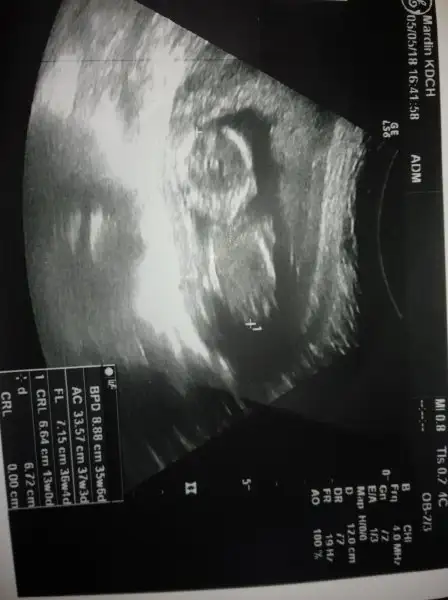

Buda benim bebeğim. Bende çok merak ediyorum cinsiyetini. Ramazan ayından önce kontrole gidecem ogrenirim o zaman inşallah.

Kız gibi geldi banaBuda benim bebeğim. Bende çok merak ediyorum cinsiyetini. Ramazan ayından önce kontrole gidecem ogrenirim o zaman inşallah.